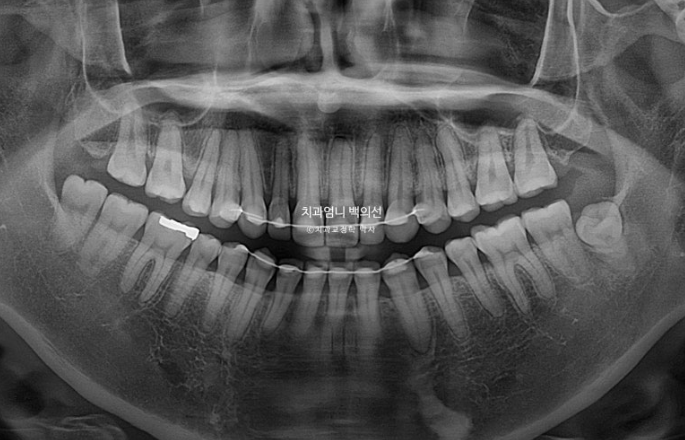

25.05

치근흡수는 보이지 않고 뿌리 배열은 좋습니다.

2년간의 치료결과 중첩을 해보면 어금니가 3mm 함입되었고 앞니가 위 아래 각각 1mm씩 정출이 되어 개방교합이 완전히 해소되었습니다.

함입된 어금니 덕에 아래턱이 더 다물리며 자가회전이 일어나서 하관이 짧아졌습니다.